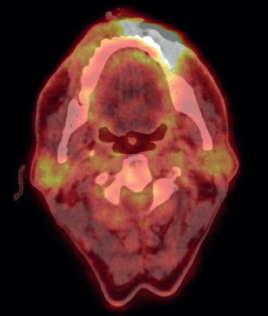

To assess the extent of the condition, an 18F-fluorodeoxyglucose positron emission tomography (PET)/CT scan was performed, revealing an Fluorodeoxyglucose (FDG)-avid left lower lip lesion measuring 4.5 × 1.5 × 2.8 cm with a maximum standardised uptake value (max) of 15.66 (Figure 2). A repeat biopsy and IHC profiling of the left lower lip lesion demonstrated positivity for CD3 and CD56, a loss of CD5 staining in CD3-positive cells, a reserved CD4/CD8 ratio and negativity for CD20, TdT and EBV status. Additionally, a Ki-67 proliferative index of approximately 50% further supported the diagnosis of P-TCL NOS (Figure 3).

Figure 2. Pre-chemotherapy PET CT scan, showing FDG avid lesion involving left lower lip.